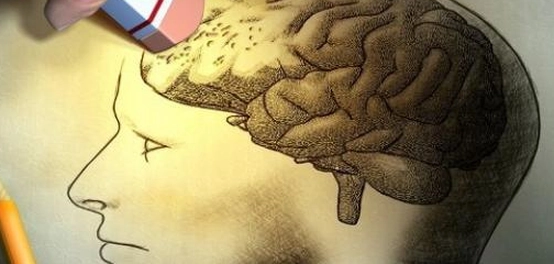

ضعف الذاكرة: نظرة عامة

يشير العديد من الأبحاث الطبية إلى أن أنماط الحياة اليومية، بما في ذلك النظام الغذائي والعادات الشخصية، تؤثر بشكل كبير على صحة الدماغ وقدرته على الاحتفاظ بالمعلومات. فإن فقدان الذاكرة لا يقتصر على كبار السن فقط، بل قد يصيب أي شخص بغض النظر عن عمره، وذلك نتيجة لأسباب متعددة تتعلق بنمط حياته.